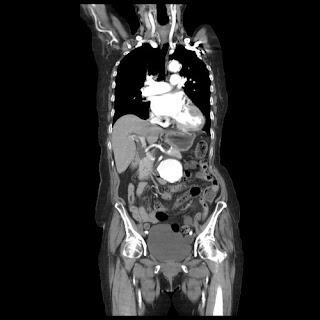

馬上安排了一個新的電腦斷層檢查

在左邊腎靜脈下面有個約5.7公分的腫瘤

不到半年就脹大了0.6公分

符合健保腹主動脈支架的給付標準

以冠狀切面來看

這個主動脈瘤局部脹大很厲害頸動脈的頸部扭了一個很大的角度

幾乎是個髮夾彎

而且因為電腦斷層每5毫米做的一個切面

剛好沒有切出來右腎動脈從腹主動脈分支出來的地方

對主動脈支架的手術的術前計畫來說有一定的難度